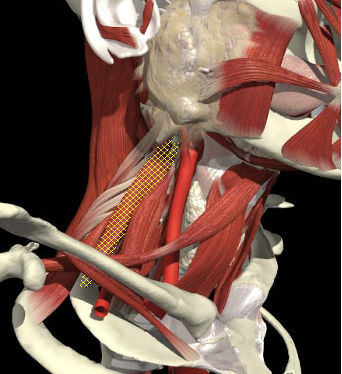

Structures to Avoid

Brachial Plexus

The BP lies inferior to a line from the posterior margin of the sternomastoid at the level of the cricoid cartilage to the midpoint of the clavicle

The BP lies inferior to a line from the posterior margin of the sternomastoid at the level of the cricoid cartilage to the midpoint of the clavicle. Scalenus medius is behind and above line.

Interscalene Groove & Brachial Plexus

Interscalene groove

Nerves in Posterior Triangle

Lies on LS, enters 1cm cranial to EP posterior border of SCM and runs on line to between middle and lower third of trapezius.

Should inject splenius and levator over 1cm above EP